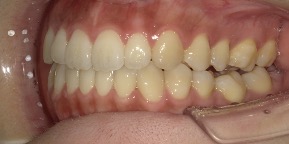

26歳女性のビフォーアフター

| 診断 | 空隙,叢生 |

| 治療方針 | 治療方針:前歯の咬合関係改善と空隙閉鎖を主な目的にて主にIPR(歯と歯の間をわずかに削合してスペースを獲得する方法)を組み込んだ動的矯正治療を行い、空隙、前歯咬合を改善後、保定を行う。臼歯部の咬合関係はプランの都合上維持することとした |

| 治療費 ※ | 69万8千円(診断、型取り、矯正中のメンテナンス、保定装置を含む料金) |

| 治療期間 | 1年8か月 |

| リスク | 1日20時間以上マウスピースを使用できない場合、歯が動かなかったり、想定しない誤差により不完全に終わる可能性がある。装着時や食事時に痛みを伴う。歯肉退縮や虫歯になるおそれがある。また、指導通りに装着できていない場合や適切なブラッシングが出来ていないとそのリスクが高くなる。歯根が短くなることがある。ごくまれに歯の神経が損傷してしまうことがある。過去にぶつけたり深い虫歯治療をしたことがあるとそのリスクはやや高くなる。矯正後には保定装置が必要。適切な使用ができない場合、後戻りの原因となる。将来的に歯並びが動いて再矯正が必要な場合がある。舌癖(舌で歯を押し出す癖)親知らずが正常に生えていない場合、その可能性がやや高くなる。 |

※ 治療費は、治療当時の費用で、現在の費用と異なる可能性があります。現在の費用は治療費のページでご確認くださいませ。